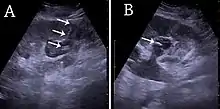

Figure 16. Hydronephrosis with dilated anechoic pelvis and calyces, along with cortical atrophy. The width of a calyx is measured on the US image in the longitudinal scan plane, and illustrated by ‘+’ and a dashed line.[1]

Figure 17. Same patient as in Figure 16 with measurement of the pelvis dilation in the transverse scan plane illustrated on the US image with ‘+’ and a dashed line.[1]